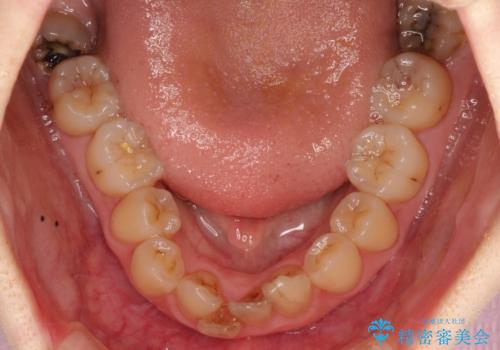

初診時の歯並びの状態としては、上下ともに前歯部の中等度のがたつきがあり、下の前歯は本来生えるはずの歯が2本生まれつき欠損している状態でした。

噛み合わせが深い過蓋咬合という状態でもあったため、下の歯の装置をつけたり、嚙み合わせを上げる(下の歯が見える状態にする)ことにたいへんに苦労した症例でした。